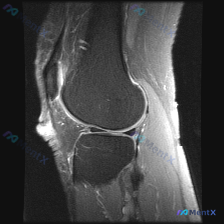

刚看到这个膝关节MRI读片的病例,有点典型,整理出来和大家分享一下思路。 病例基础信息 这是一份膝关节矢状位MRI影像,序列为T2WI或PDWI-FS,对软组织、水肿、韧带病变显示清晰。 影像学核心发现 1. 骨骼与关节软骨:髌骨后方关节软骨面不平整,髌骨软骨下骨可见片状高信号影,提示骨髓水肿或软骨...

刚刚整理了一份很有启发的膝关节MRI读片病例,分享给大家,这个病例最有意思的点就是预设问题和实际影像发现不一致,很考验读片思路。 病例基础信息 这是一张膝关节矢状位T2加权MRI图像,需要评估是否存在半月板异常,图像质量清晰,能看到股骨远端、胫骨近端、髌骨、髌下脂肪垫、关节间隙等全部关键结构。 影像...

刚看到一个很有代表性的读片病例,临床怀疑膝关节软骨异常,给了单幅膝关节矢状位T2加权MRI,整理一下分析思路分享给大家。 病例基本信息 - 临床问题:标识图像显示的异常是否为软骨异常 - 影像资料:单幅膝关节矢状位T2加权(或脂肪抑制质子密度加权)MRI,图像质量好,无运动伪影,覆盖股骨远端、胫骨近...